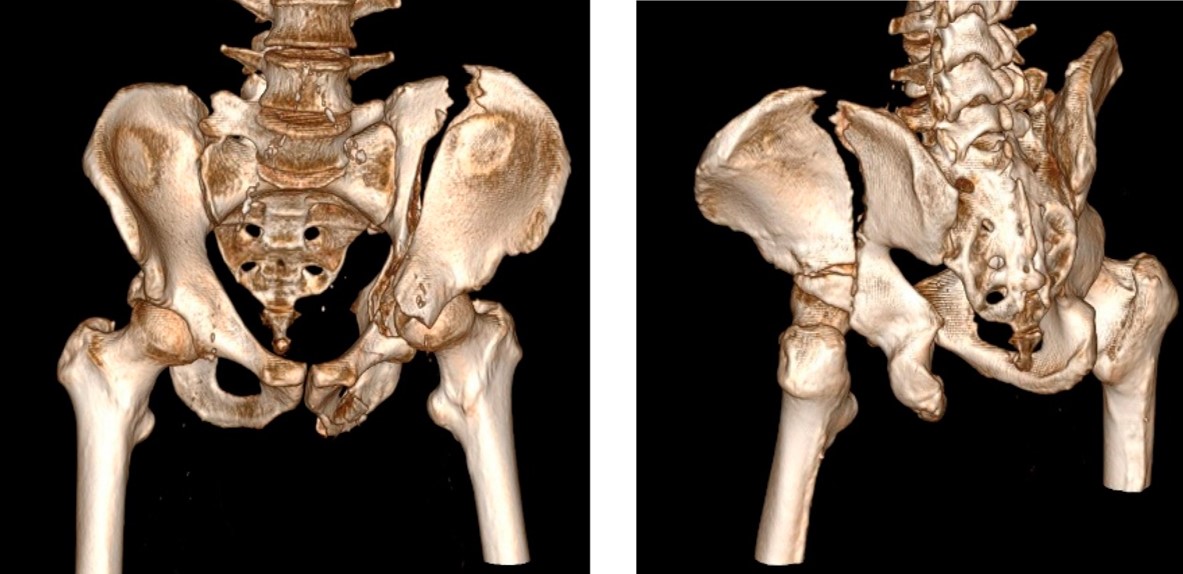

Pelvis & Acetabular Fracture

High-energy trauma fractures involving the pelvic ring or the acetabulum (hip socket). Frequently associated with life-threatening bleeding, visceral injuries, and long-term complications such as avascular necrosis or post-traumatic arthritis. Require specialized surgical reconstruction and multidisciplinary management.

High-energy trauma ORIF / acetabular reconstruction Multi-disciplinary care Risk of AVN & arthritis